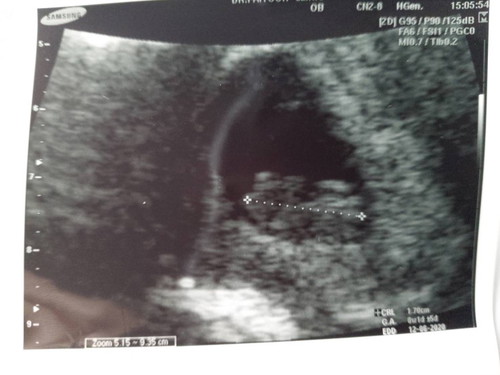

ในแอพบอก 8W 4D แต่วันนี้ไปซาวด์มาคุณหมอบอก 8W 1D แบบนี้อันไหนชัวร์กว่ากันคะ

ถ้าเป็นคนที่ประจำเดือนตรงเป๊ะๆตลอด หมอจะให้ยึดจากกำหนดที่หมอคำนวนให้ (นับจากวันแรกของปจด.ครั้งล่าสุด) จ้า เพราะในใบซาว แต่ละครั้งกำหนดจะคลาดเคลื่อนไปมาได้ เพราะมันคาดคะเนจากขนาดตัวทารกจ้า ((แต่ถ้าเป็นคนที่ประจำเดือนไม่ตรง ไม่สม่ำเสมอ ก็ต้องยึดจากใบซาวด์ค่ะ ซึ่งแต่ละหนคลาดเคลื่อนได้ค่ะ อย่างที่บอกไปข้างบน)) ปล; ต่างกันแค่ 3 วันเองค่ะ ปกติอายุครรภ์จากผลซาวด์ +/- ได้ถึง 7-14 วันค่ะ